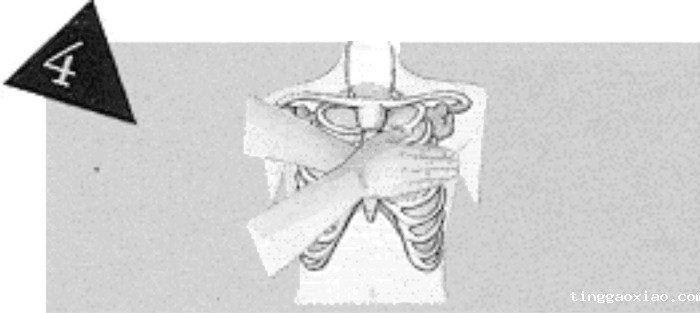

施救者面向病人跪着,两腿打开,与肩同宽,肩膀在伤患胸骨的正上方,双臂伸直,用体重的力量,直接下压,压力推至胸骨上。

每次下压时,应将胸骨压下4~5厘米,放松时,手不施压力,但不可移动手的位置。